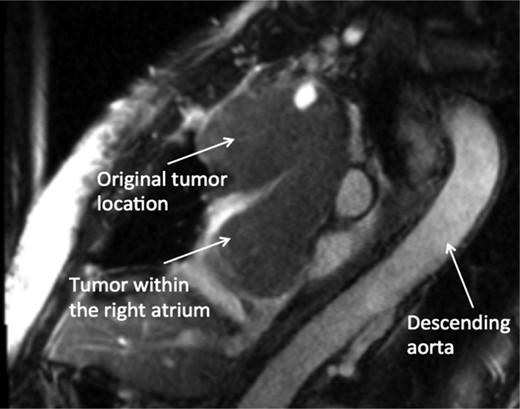

A 74-year-old female presented with facial and upper extremity swelling over the last month. The swelling was worse in the morning and improved throughout the day. The patent also reported dyspnea on exertion. A review of systems was otherwise negative. Social history was notable for 40-pack-year smoking history, but she quit smoking 12 years ago. Her vital sign were stable. Physical examination revealed mild facial swelling, non-pitting edema of the upper extremities and distention of superficial veins of the anterior chest wall and jugular veins. There were no significant laboratory abnormalities. An echocardiogram showed moderate right atrial dilation with a mobile mass in the atrial cavity prolapsing through the tricuspid valve, bowing of atrial septum from right to left consistent with increased right atrial pressure, moderate tricuspid regurgitation and normal left ventricular ejection fraction with no regional wall motion abnormalities. Cardiovascular magnetic resonance imaging revealed a 9.9 × 4.3 cm heterogeneous mass admixed with thrombus in the anterior mediastinum compressing the SVC and endovenously extending into the right atrium (Figs 1–3). Anticoagulation with heparin drip was initiated. A computed tomography (CT)-guided biopsy revealed a tan-colored mass with CD5 lymphocyte predominance, inconspicuous epithelial cells positive for P63 expression and cytokeratin AE1/AE3 that was morphologically consistent with thymoma type B1.

CMR axial four-chamber view: mass in the right atrial cavity protruding through the tricuspid valve into the right ventricle.